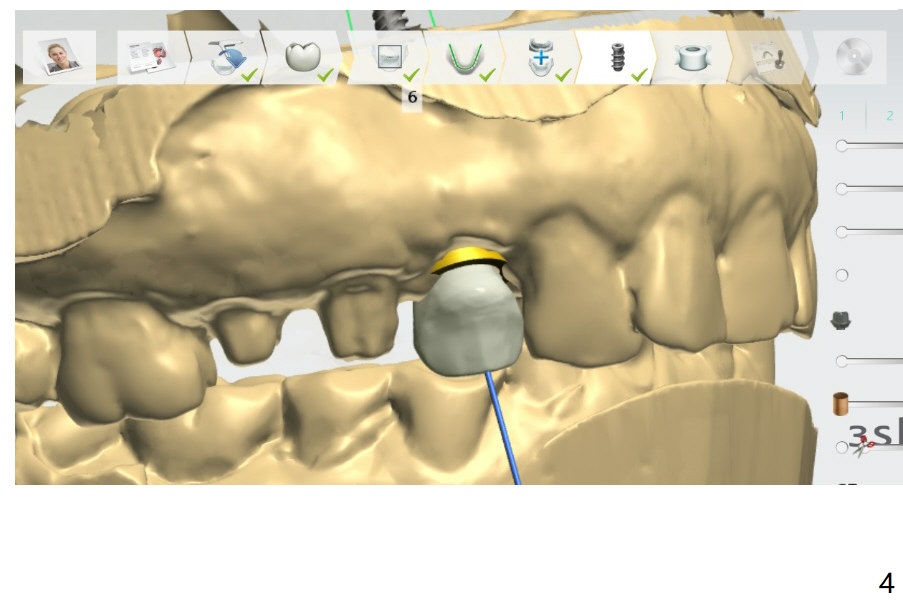

Partially Guided Surgery

Because of the narrow ridge and short bone, try in the guide, anesthetize (double anesthetics), start initial osteotomy with the guide and lay flaps for #6 impacted tooth removal. Use IS mini implant kit to finish the osteotomy free hand, hopefully entering the upper border of the extraction socket for 2-pointed fixation. Find the surgical stent for possible new temporary FPD.